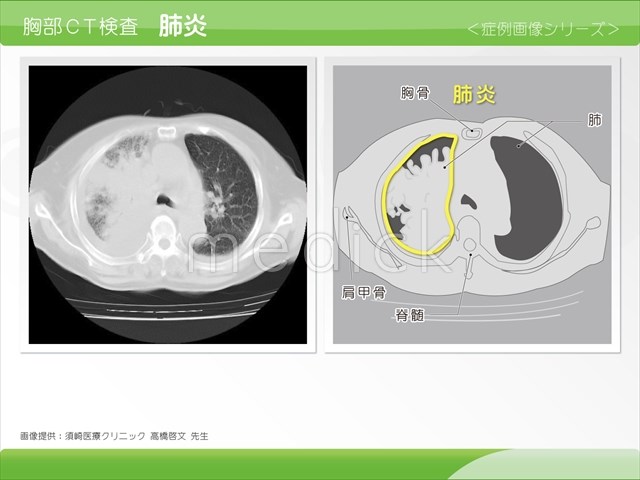

NMC Diagnosis。0b3b59392e9eaf6a38d2ac37cd75fc。間質性肺炎 | 印西そよかぜ内科・呼吸器内科。画像診断 Vol.41 No13. 特集『なぜによくわからない間質性肺炎。「肺炎の画像診断と最新の診療」藤田次郎定価: ¥ 12,540#藤田次郎 #本 #BOOK #健康 #医学